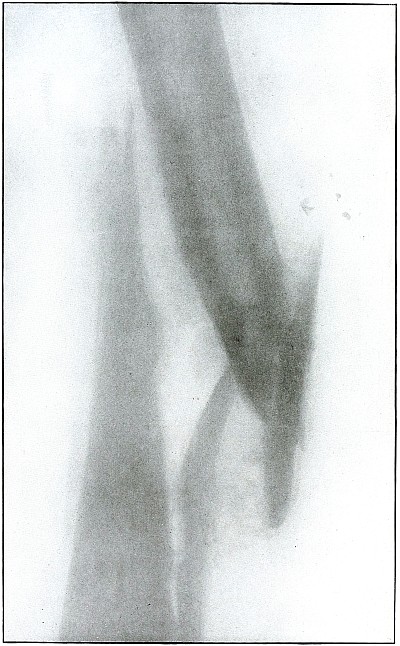

Plate 60.

_

[Pg 131]

Rifle—Plate 60.

LOWER EXTREMITY.

Gunshot Fracture of the Tibia and Fibula,

with Lodgment of the Missile.

The course of the bullet was diagonal from within outward and backward about the middle of the leg, with the impact tangential on the tibia and direct on the fibula. The bullet lies just behind the tibia.

It is apparent that the bullet has been greatly deformed and that its jacket has been badly torn from the core. The force of impact on the object from which it ricocheted must have been contributed by the velocity of short range, which reduced the striking energy so greatly that the bullet was lodged by the resistance of the tibia and fibula.

The wound was not infected, and callus formation shows that repair has begun.

The treatment in such cases, without infection, is noninterference. The lodgment of the missile need not prejudicate the prognosis, and certainly the additional damage in the search for the bullet is not warranted, except under special indications. [Pg 132]